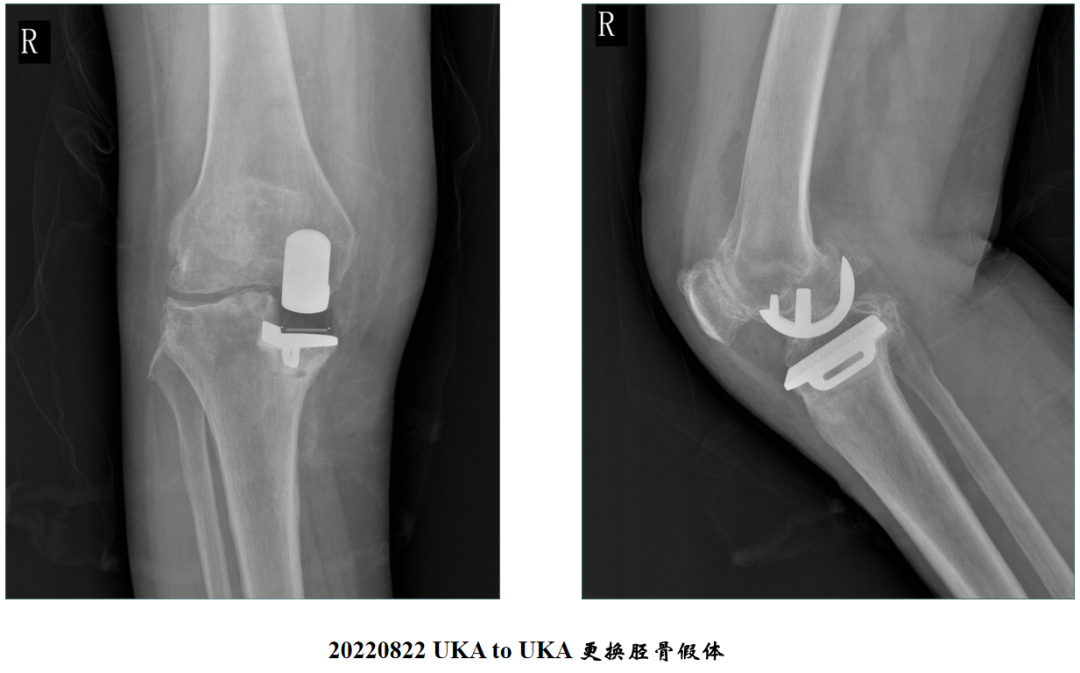

病例1:胫骨假体翻修

UKA to UKA 更换胫骨假体